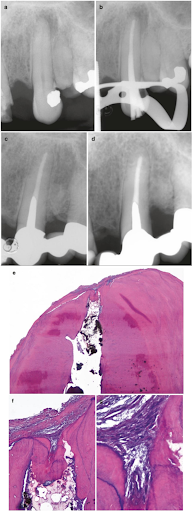

(a) Răng nanh hàm trên hoại tử tủy và viêm quanh chóp không triệu chứng ở 1 bệnh nhân nam 41 tuổi. (b) Ống tủy được sửa soạn và băng thuốc với Ca(OH)2. 1 tuần sau răng được trám bít ống tủy bằng phương pháp nhồi dọc với GP và cement bít. (c) XQ kiểm tra sau 9 năm có thể thấy tình trạng mô quanh chóp bình thường. Răng không có triệu chứng. (d) 19 năm sau bệnh nhân trở lại với triệu chứng sưng nướu mặt ngoài. Thăm dò cho kết quả độ sâu túi nha chu mặt ngoài là 8 mm. XQ kiểm tra cho thấy 1 khiếm khuyết xương ở góc xa. Lưu ý hình ảnh mô quanh chóp vẫn rất bình thường. Răng được chẩn đoán là gãy dọc và đã được nhổ bỏ. (e) Lát cắt ở gần trung tâm ống tủy, bao gồm cả đoạn ống tủy chóp và lỗ chóp (foramen). Quan sát thấy sự hiện diện của mô bị canxi hóa ở đoạn ống tủy cận chóp (nhuộm hematoxylin và eosin). (f) Hình ảnh chi tiết foramen. Hiện tượng canxi hóa mô xảy ra và lấn chiếm đoạn ống tủy cận chóp này giống như cement, và nó bị cắt ngang bởi 1 dải sợi mô liên kết. Mô nha chu còn sót lại trên bề mặt chóp chân răng khi nhổ răng ra thì thấy không bị viêm. (g) Hình ảnh chi tiết mô mềm tại foramen. Chỉ quan thấy các nguyên bào sợi và sợi collagen, không hề có tế bào viêm nào.